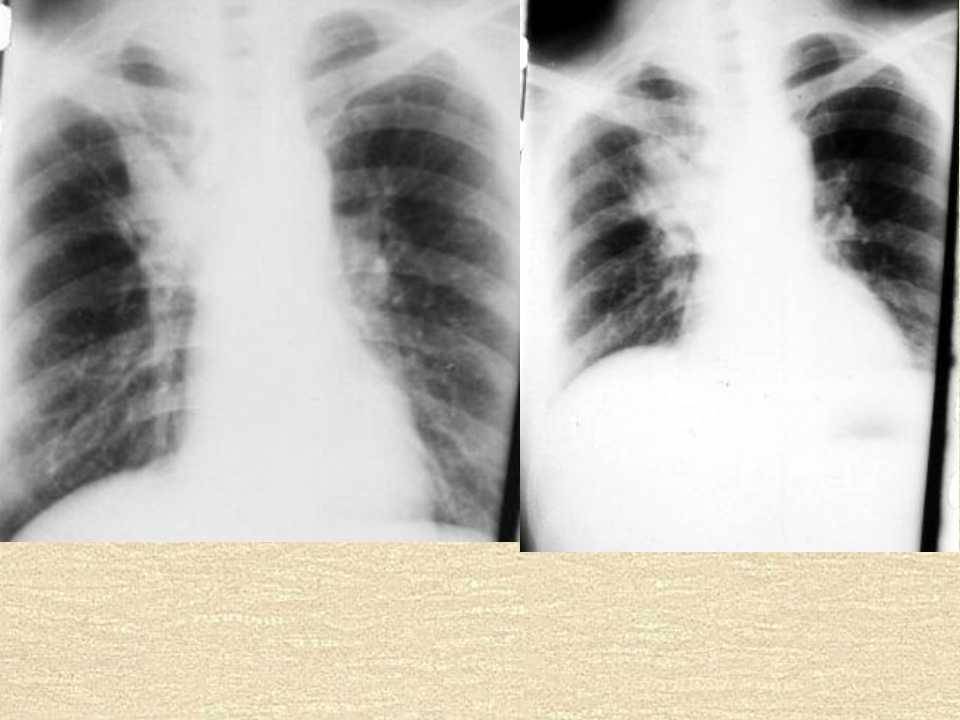

肺癌影像学表现